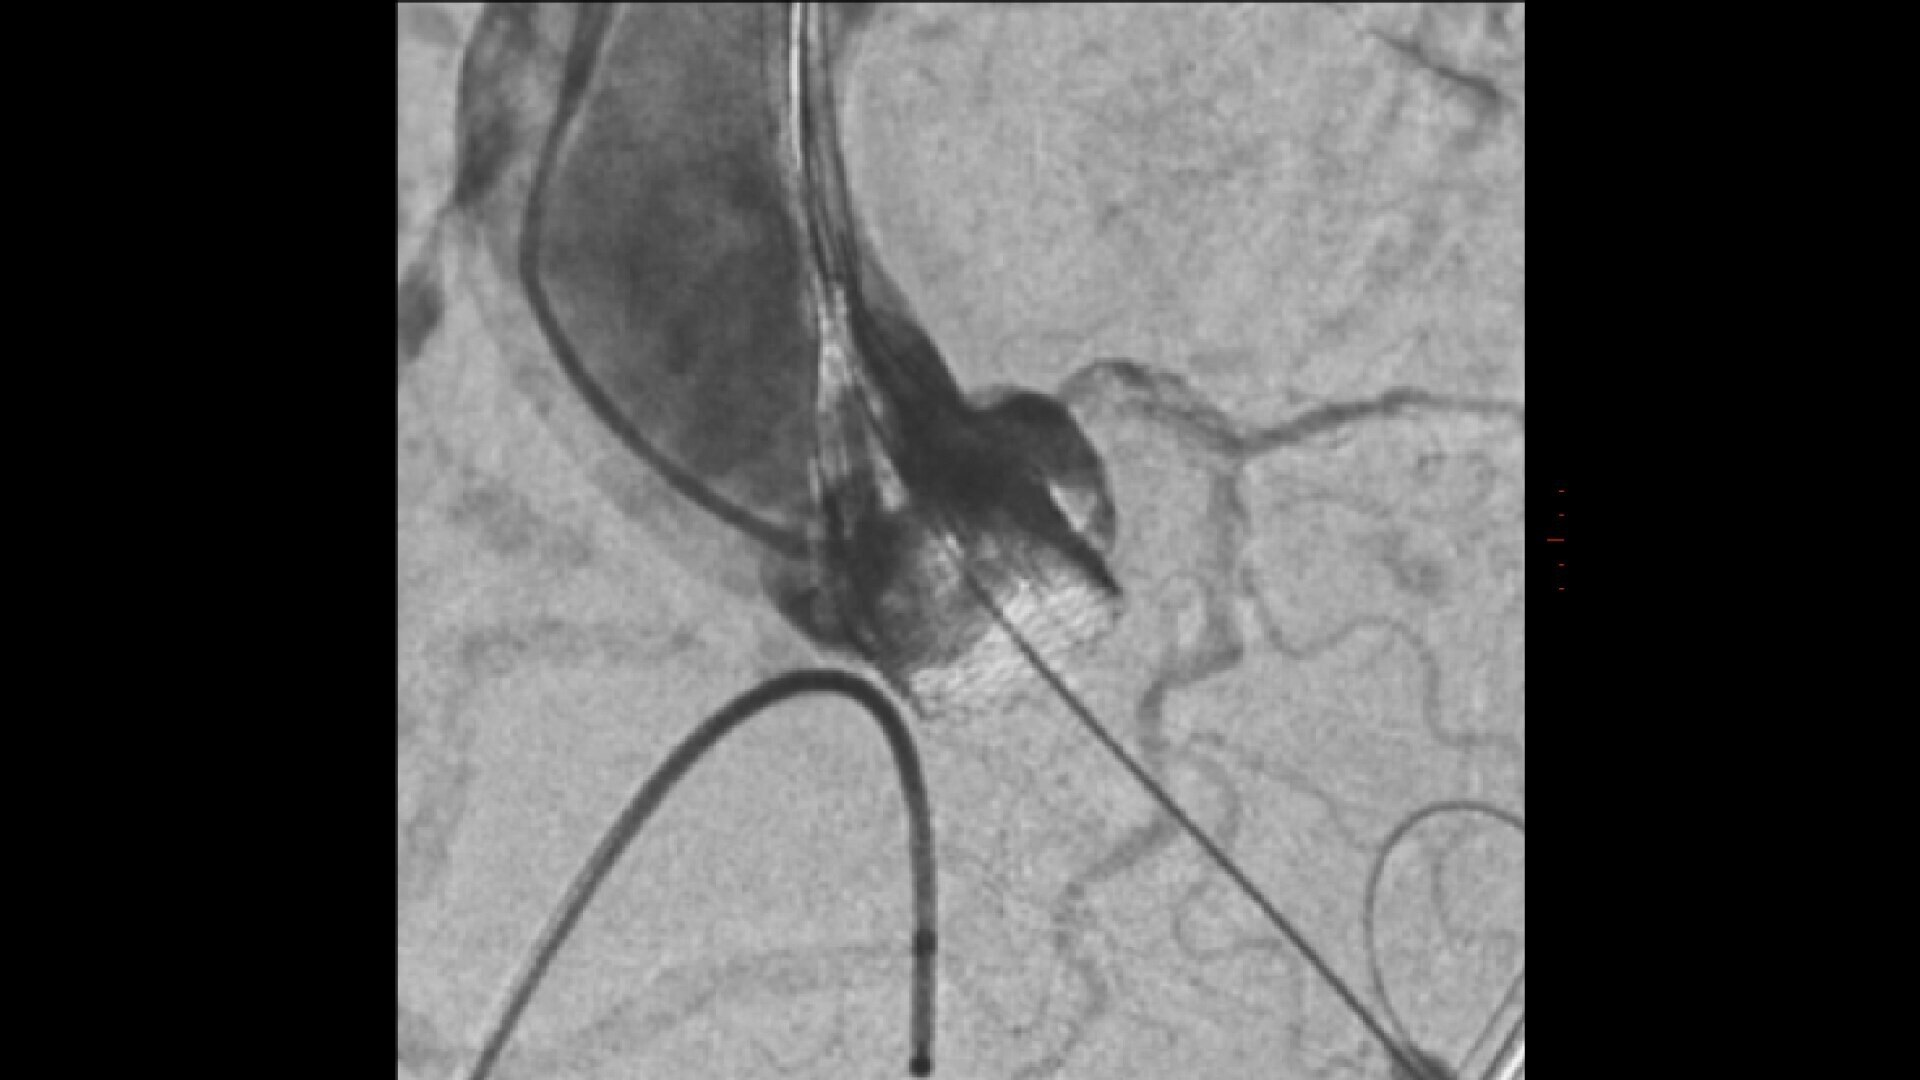

Transcatheter aortic valve implantation

Streamlined workflow for your TAVI procedures

GUIDE

3D fusion guidance enhanced with Calcification Enhancement improves the visualization of moving contrasted structures.

Assess potential regurgitation with exceptional contrast visualization.